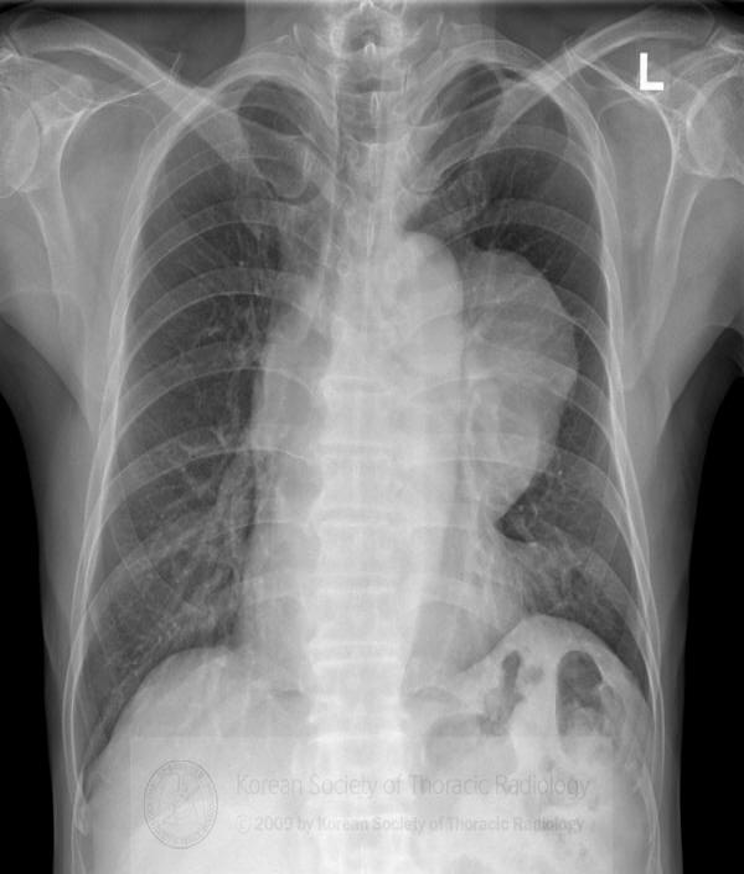

differential diagnosis for an anterior mediastinal mass includes:

1. Thymoma

2. Thyroid & parathyroid

3. (Terrible) Lymphoma

4. Teratoma

5. Thoracic aorta  (5 Ts)